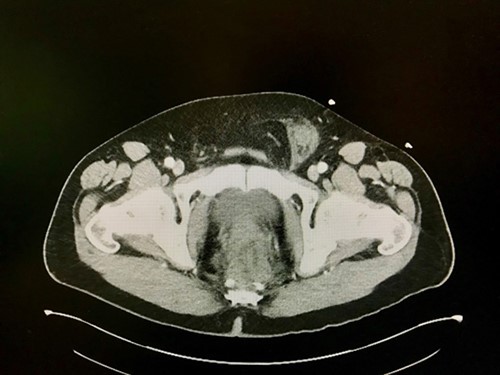

On postoperative day seven, the patient reported new onset of severe pain in the left groin. Physical exam confirmed an irreducible, tender bulge suspicious for an incarcerated inguinal hernia. CT scan of the abdomen and pelvis (Figure 3) confirmed fat containing inguinal hernia with standing and inflammatory changes.

Figure 3. CT scan revealing incarcerated left inguinal hernia with tissue stranding.

The patient was thereafter admitted to the operating room for emergent laparoscopic hernia repair, which confirmed an incarcerated fat containing direct and indirect inguinal hernia. The hernia was reduced laparoscopically with 3D-mesh enforcement. The postoperative period was uneventful, and the patient was discharged home.